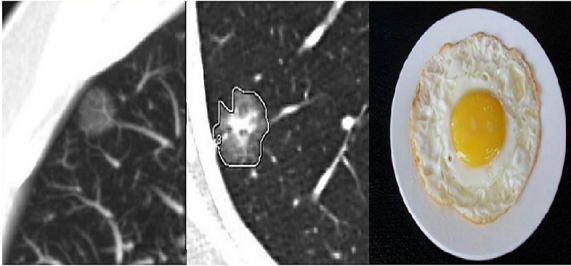

2、局限性与弥漫性GGO

局限性与弥漫性GGO是因病灶范围大小的不同而划分,局限性GGO的病灶仅表现为一个或多个结节,而弥漫性GGO表现为大片状磨玻璃影。

图三 局限性与弥漫性GGO对比